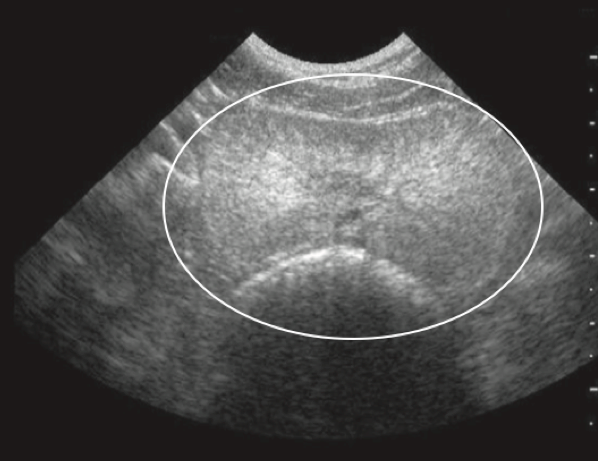

由超音波檢查攝護腺時,良性攝護腺肥大增生時,攝護腺會對稱性且均值地曾厚,但如果出現囊泡樣增生、外型不對稱、結構改變,如下圖,可能需要藉由細針採樣,將部分攝護腺細胞透過顯微鏡觀察型態,以區分良性增生、惡性增生、感染等情形。

圖一、攝護腺良性增生